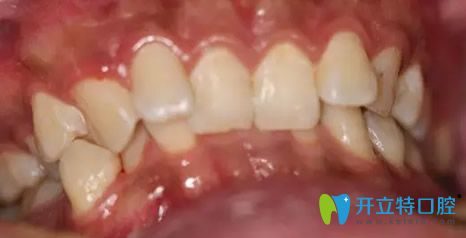

口腔牙齿矫正案例:

病例:牙齿排列不整齐,门牙凹凸不齐,影响美观。

治疗方案:隐形无托槽矫正。